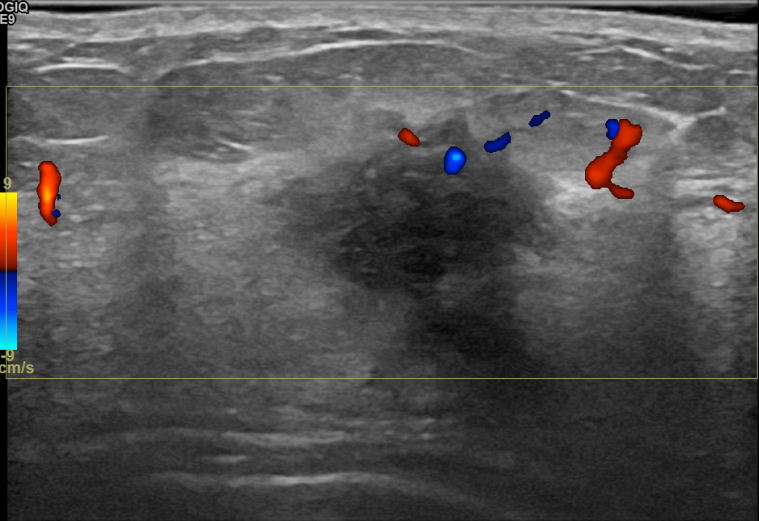

상기환자는 외부검진이상으로 내원하신 40대초반

여성분으로 의심스러운 좌측혹 조직검사 시행해 침윤성암으로 진단되었습니다